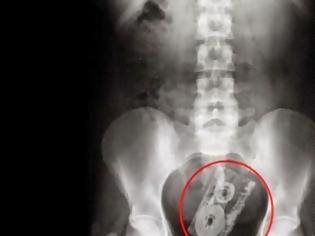

μια παραμάνα, ένα κλειδί και ένα πιρούνι

Δεν πίστευαν στα μάτια τους οι γιατροί όταν έβλεπαν τις παραπάνω ακτινογραφίες. Μέσα στο στομάχι των ασθενών τους βρέθηκαν μια παραπάνα, ένα κλειδί αλλλά και ένα πιρούνι.

ΔΕΝ ΘΑ ΠΙΣΤΕΥΕΤΕ ΣΤΑ ΜΑΤΙΑ ΣΑΣ....Δείτε τι αφαιρούν από το στομάχι ασθενών χειρουργοί! -ΦΩΤΟ - Φωτογραφία 5  ΔΕΝ ΘΑ ΠΙΣΤΕΥΕΤΕ ΣΤΑ ΜΑΤΙΑ ΣΑΣ....Δείτε τι αφαιρούν από το στομάχι ασθενών χειρουργοί! -ΦΩΤΟ - Φωτογραφία 7